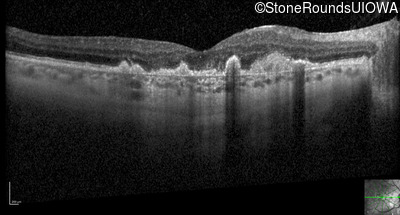

Optical Coherence Tomography - Right - 20/250

Exemplar / OCT Stack